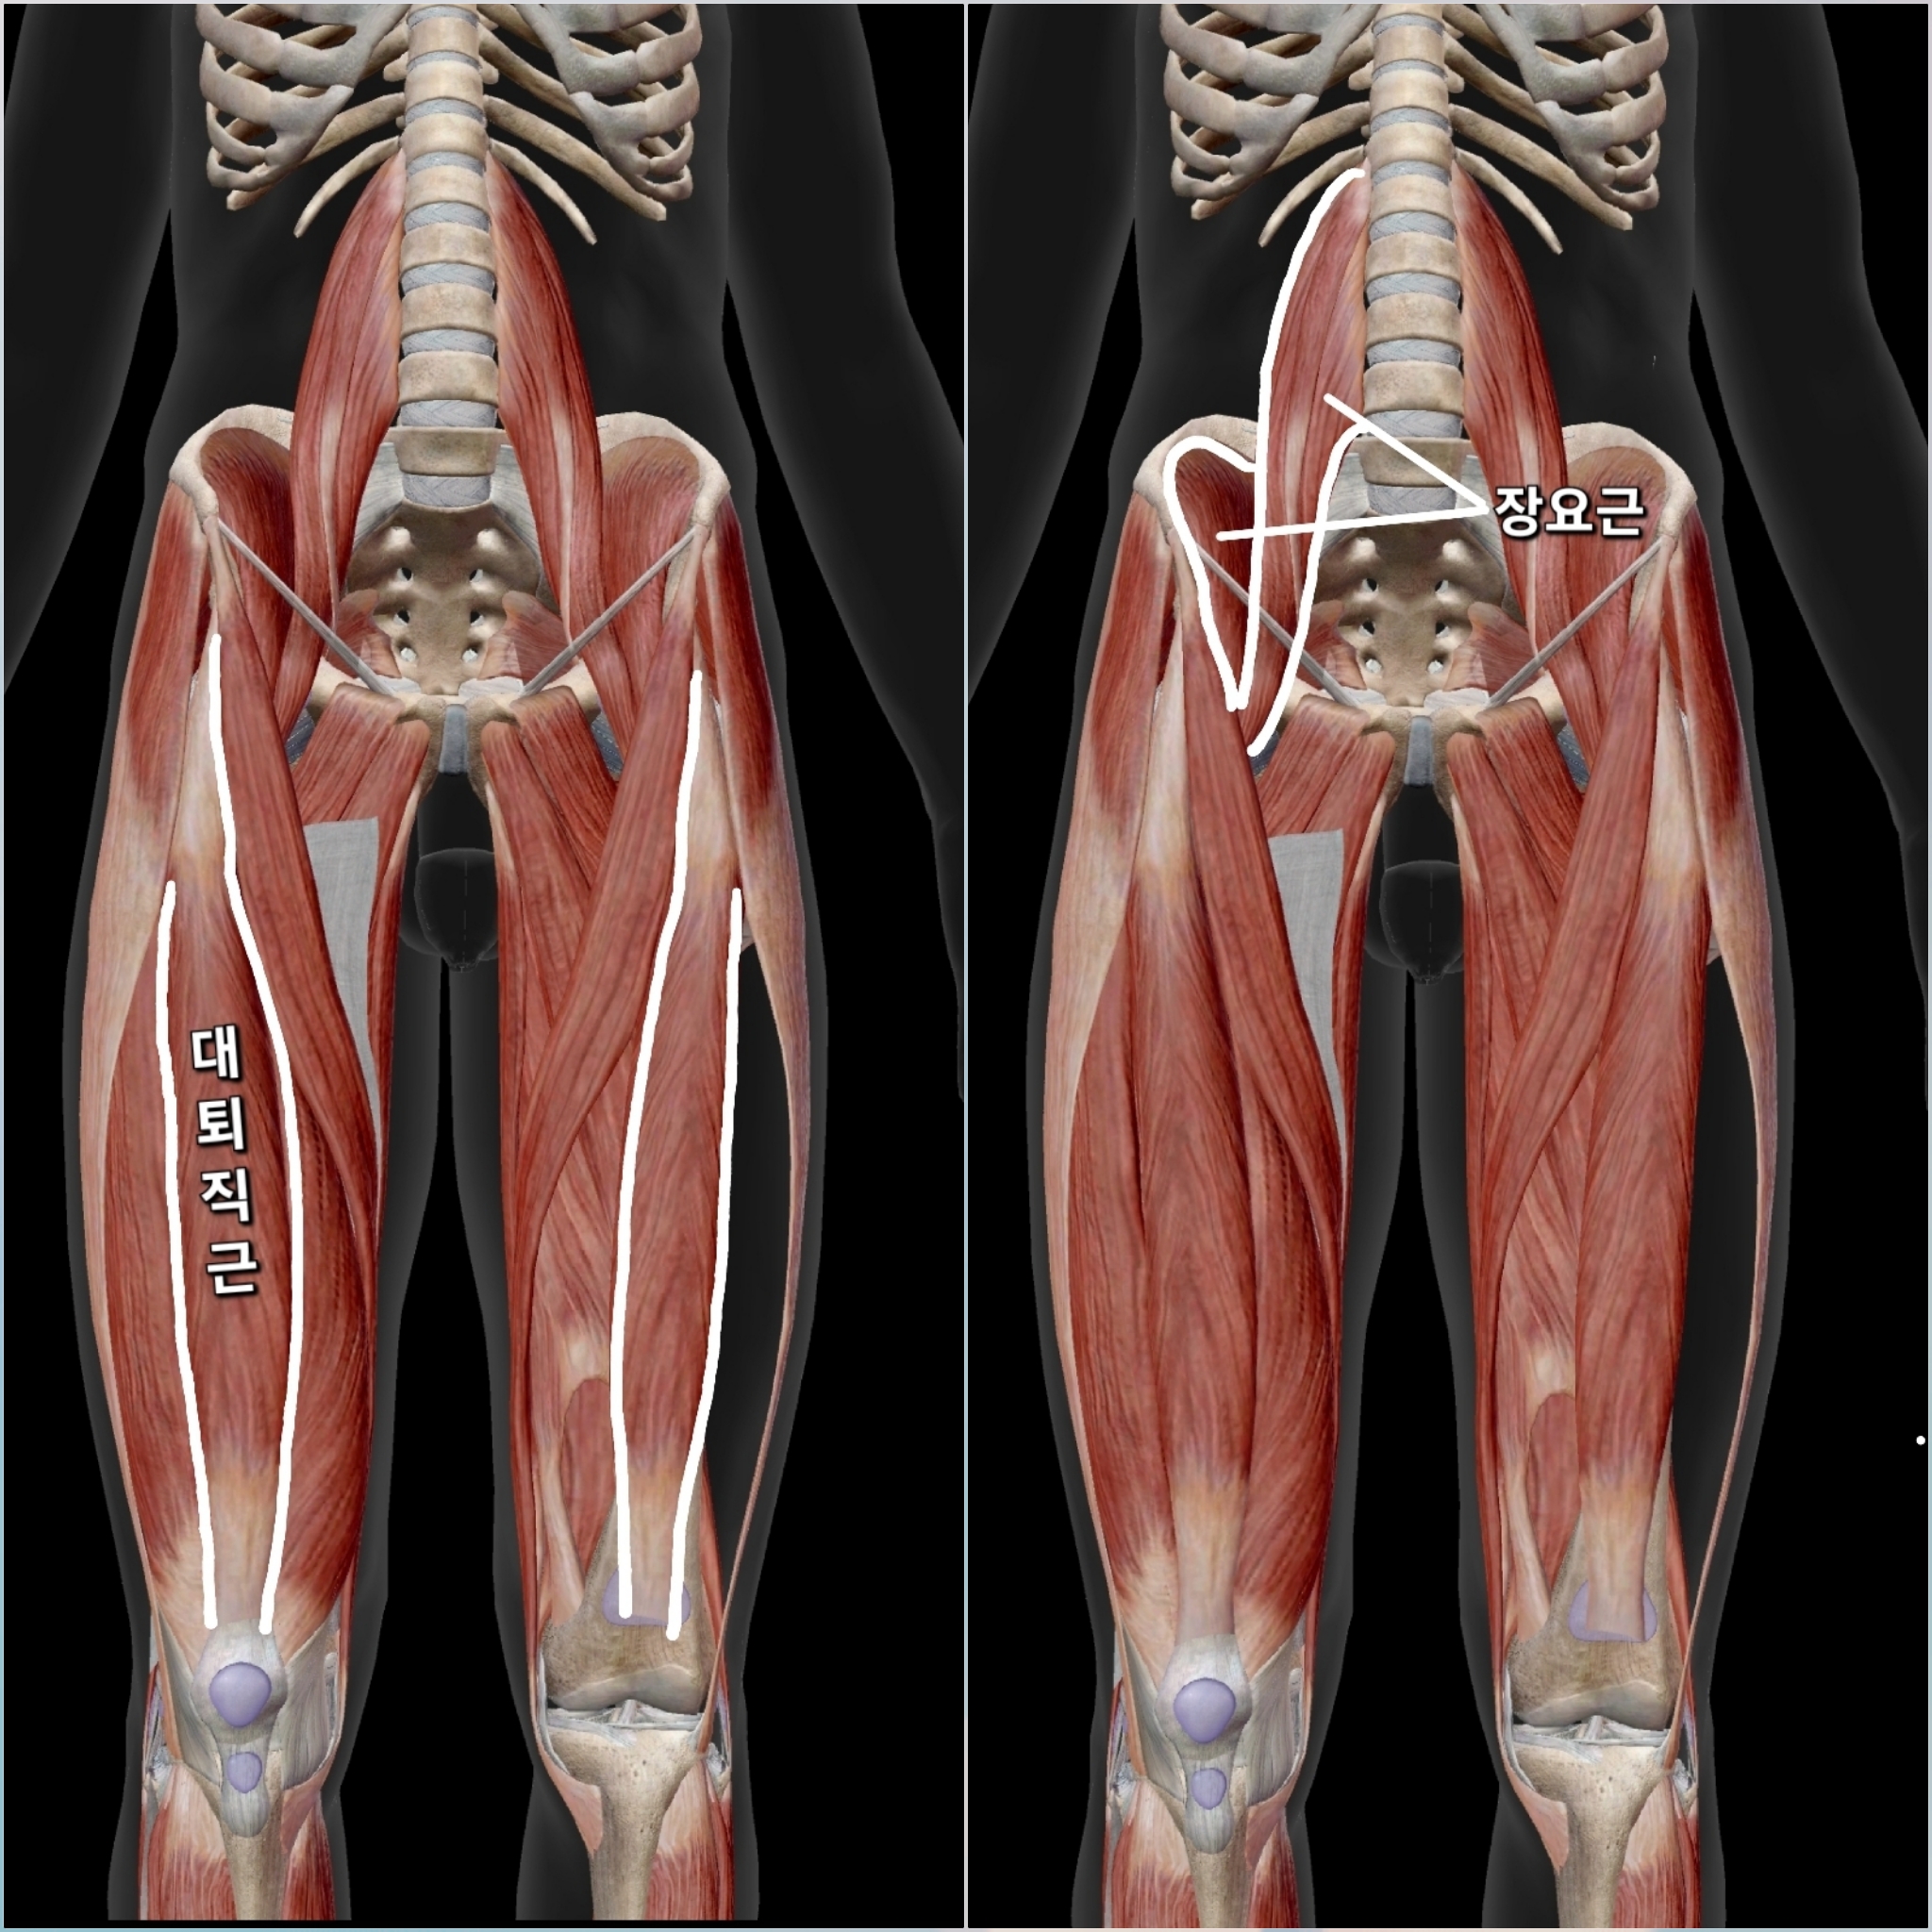

ㆍ대퇴사두근(Rectus Femoris, Vastus Muscles)은 허벅지 앞쪽의 근육으로, 무릎을 펴고 고관절을 굽히는 역할을 합니다 양반다리시 고관절을 외회전(바깥으로 돌림) + 외전(옆으로 벌림) + 굴곡(팬티라인주름 깊게 접는 동작) 같은 움직임이 필요합니다 허벅지앞쪽근육인 대퇴사두근이 과긴장 된 경우 이 움직임을 방해하면서 허벅지 앞쪽에 통증을 유발할 수 있습니다 특히 허벅지앞쪽 근육 중에서 대퇴직근(Rectus Femoris)은 고관절과 무릎을 동시에 조절하는데, 이 근육이 뻣뻣하면 고관절이 구부러질 때 (팬티라인접을때)과도한 장력이 발생하면서 허벅지 앞쪽이 당길 수 있습니다 쉽게 말하면 양반다리시 허벅지앞쪽근육이 늘어나줘야 하는데 긴장상태로 늘어나지 못해 통증이 나타나는 겁니다 양반다리 상태에서 무릎이 바닥 가까이 안 닿고 떠 있는 경우 대퇴사두근이 유연하지 않아서 허벅지 앞쪽이 긴장된다는 신호일 가능성이 큽니다

ㆍ장요근(Iliopsoas)은 허리와 대퇴골을 연결하는 근육으로 장요근은 고관절을 굴곡(구부리기)하고, 살짝 내회전(안으로 돌리기)하는 역할을 합니다 하지만 고관절이 외회전(바깥으로 돌리기)되거나 외전(벌려지기)되는 움직임과 함께 굴곡될 때는 장요근은 본래의 기능을 수행하지 못하고 오히려 늘어나게 됩니다 특히 다리를 바닥에 최대한 붙이려고 할수록 장요근이 더 늘어날 가능성이 큽니다 장요근이 늘어나야 하는데, 단축된 경우 이 움직임이 제한되면서 양반다리 허벅지 통증이 생길 수 있습니다

ㆍ대퇴직근은(Rectus Femoris) 고관절을 굽히면서 무릎을 펴는 역할을 하는데, 양반다리를 하면 고관절이 굽혀지고 무릎이 구부러지는 상태가 됩니다 대퇴직근이 짧으면 무릎을 구부려 앉는 양반자세가 어려워집니다 억지로 양반다리로 앉게 되면 근육이 과도하게 당겨지면서 양반다리 골반통증이 허벅지 앞쪽으로 발생됩니다 양반다리 허벅지통증시 대퇴직근의 단축을 의심해 봐야 합니다